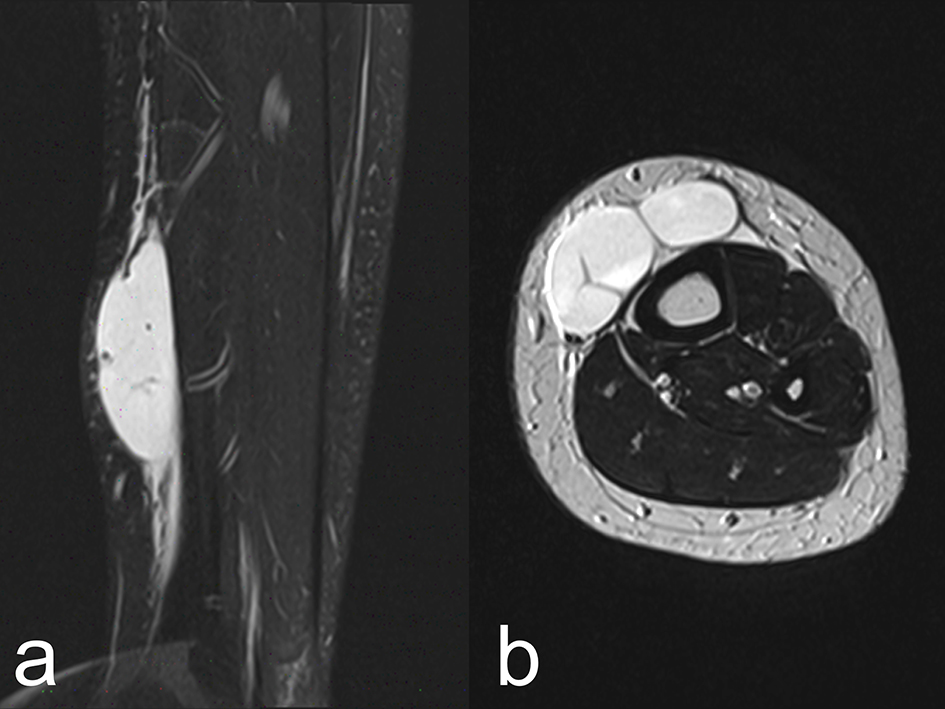

![]() Click for large image | Figure 2. Magnetic resonance T2-weighted images show a hyper-intense mass separated by septum, containing debris. (a) Sagittal section. (b) Axial section. |

The patient, now an 18-year-old Japanese girl, first presented with NS at the age of 2 years. She has been treated with prednisolone according to the International Study of Kidney Disease in Children protocol [3] and promptly responded with resolution of NS. Withdrawing doses of prednisolone, she repeatedly relapsed and had never been off prednisolone. The renal biopsy showed minimal-change lesion. Cyclophosphamide treatment for 12 weeks at a dose of 2 mg/kg/day [4] failed to reduce her experiencing relapses. Relapses were treated with pulse steroid (500 mg of methylprednisolone IV for 3 days) followed by oral prednisolone [4]. After high school enrollment, she still showed steroid dependent and frequently relapsing NS. Her kidney function remained normal after 16 years follow-up. She was belonged to a softball team in her school and enjoyed playing catcher. Playing a game, a large softball accidentally hit her left tibia. A few days later, she noted a soft tissue mass at the left tibia. She thought that it must be usual tibial edema associated with NS. Serum total protein was 4.4 g/dL, albumin was 1.3 g/dL, and proteinuria was 3+. She had another relapse. After archiving complete remission of NS with reduction of weight from 51 to 46 kg, the subcutaneous mass did not improve. White blood cell count was 5,100/mm3 and C-reactive protein was 0.3 mg/dL. A 5 × 7 cm soft tissue mass was located at the left lower tibia without tenderness (Fig. 1a). Roentgenography revealed no fracture of the tibia (Fig. 1b). Magnetic resonance imaging (MRI) showed posttraumatic soft tissue cysts (Fig. 2a, b). By a needle puncture, clear 40 mL of fluid was withdrawn, but no culture was obtained. After the puncture, the subcutaneous tumor promptly shrank and no flare-up occurred.

First, the soft tissue mass is not tibial edema, but posttraumatic seroma. After archiving complete remission with 5 kg of reduction of weight, the subcutaneous mass showed no improvement; otherwise, it had to be gone. Relapses of NS occurred almost every month and she suffered from tibial edema. She must misunderstand the subcutaneous mass as usual pitting edema at the tibia because of no tenderness and arthralgia. No fracture of the tibia was noted and MRI confirmed a diagnosis of posttraumatic seroma in the tibia.